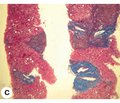

Авторы:

Михеев Ю.А.(1), Евсеев А.В.(2), Канаки А.В.(3)

(1) — ГУ «Запорожская медицинская академия последипломного образования Министерства здравоохранения Украины», г. Запорожье, Украина

(2) — Запорожский государственный медицинский университет, г. Запорожье, Украина

(3) — КУ «Запорожское областное патологоанатомическое бюро», г. Запорожье, Украина

Журнал "Гастроэнтерология" Том 51, №4, 2017